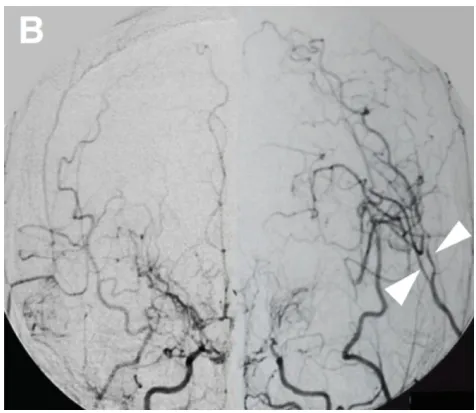

图3B:术后20天血管造影显示旁路通畅(箭头)